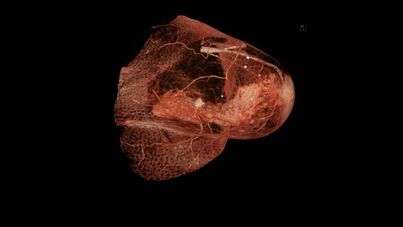

تتضمن الجراحة الإزالة المادية للورم، عادةً مع بعض الأنسجة المحيطة. قد يتم أخذ خزعة واحدة أو أكثر من العقد الليمفاوية أثناء الجراحة؛ يتم إجراء أخذ عينات العقدة الليمفاوية بشكل متزايد بواسطة خزعة العقدة الليمفاوية الحارسة.

- استئصال الثدي: إزالة الثدي بالكامل.

بمجرد إزالة الورم، يمكن إجراء جراحة إعادة بناء الثدي، وهو نوع من الجراحات التجميلية، إذا رغب الشخص، لتحسين المظهر الجمالي للموقع المعالج. بدلاً من ذلك، تستخدم النساء الثدي الاصطناعي لمحاكاة شكل الثدي تحت الملابس، أو اختيار الصدر المسطح. يمكن استخدام الحلمة التعويضية في أي وقت بعد استئصال الثدي.